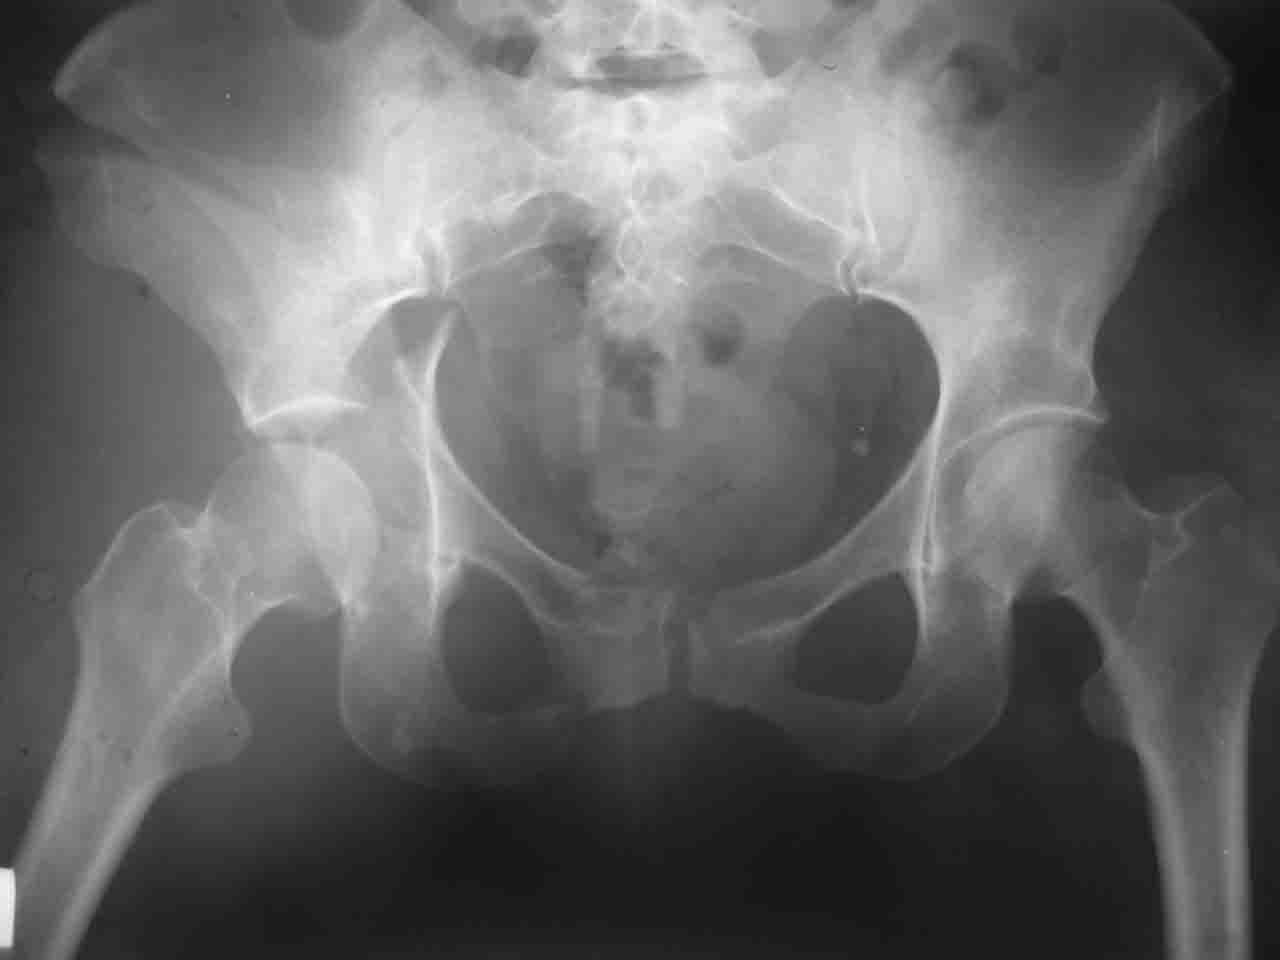

Уважаемые коллеги,43 летний мужчина, попав в автоаварию 13.10.2004, получил оскольчатый перелом обеих колонн левой вертлужной впадины.

На рентгенограммах - высокий двухколонный перелом вертлужной впадины с нарушением конгруэнтности, имеется обратная клиновидность суставной щели.